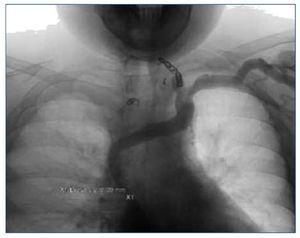

Al mes se realizó angioplastia de VCS y se consiguió dilatar hasta 12 mm con buen resultado y sin necesidad de stent (figura 2), y a los 2 meses una nueva EDA de control observa mejoría del calibre de las varices.

Figura 2. Resultado tras angioplastia de vena cava superior.